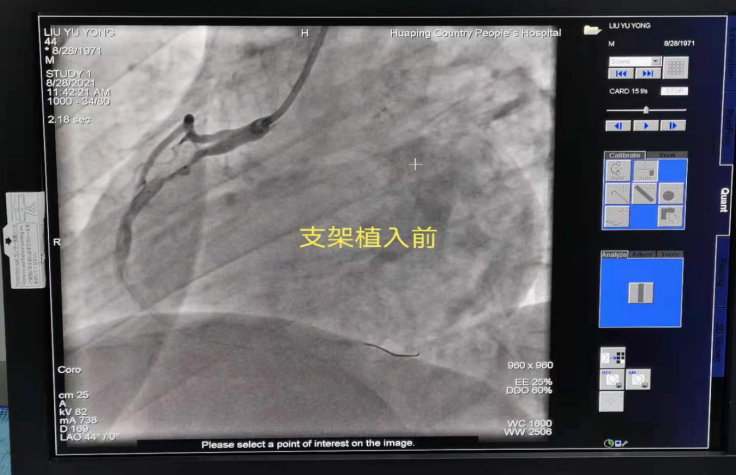

支架植入前后对比

在专家指导下,从8月27日到29日成功完成了20例心脏冠状动脉造影检查、5例心脏冠脉支架植入、3例颅脑动脉造影检查、2例心脏冠状动脉药物球囊植入、1例永久性心脏电生理起搏器植入,其中做了1例急诊冠状动脉造影+支架植入。所有患者在术中术后安全、平稳、顺利,痛苦较小,术后各种不适症状明显减轻。此次介入检查治疗的各项工作受到患者及家属的良好评价。